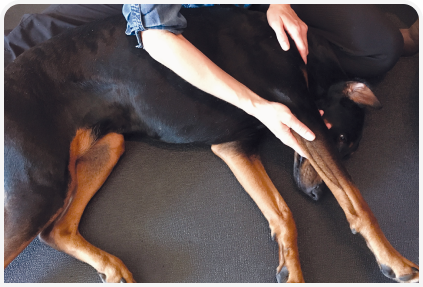

Доступная методика обследования опорно-двигательного аппарата и регулярные осмотры или «анализ спортивных качеств» служебных собак позволят выявлять повреждения костей и мышц на раннем этапе (Таблица 2), (Рисунок 11). Эти травмы могут стать причиной снижения эффективности работы животного из-за болевых ощущений или быстрого развития заболевания, вызванного разрывами и износом тканей.

Драйв и адреналин у служебных собак часто маскируют первые симптомы травмы. Нередко легкие повреждения с трудом поддаются диагностике, поскольку изменения тканей минимальны. У людей выявлению таких травм способствует чувство дискомфорта. Важно, чтобы кинологи регулярно проводили быстрый пятиминутный осмотр после напряженной рабочей смены (Таблица 3).

Частые пальпации позволяют понять, что значит «норма» для собаки, а это повышает вероятность раннего выявления незначительных изменений (Рисунок 12). Умение своевременно диагностировать травму неоценимо, оно помогает успешному лечению и предупреждает превращение незначительных повреждений в хронические состояния, мешающие работе.